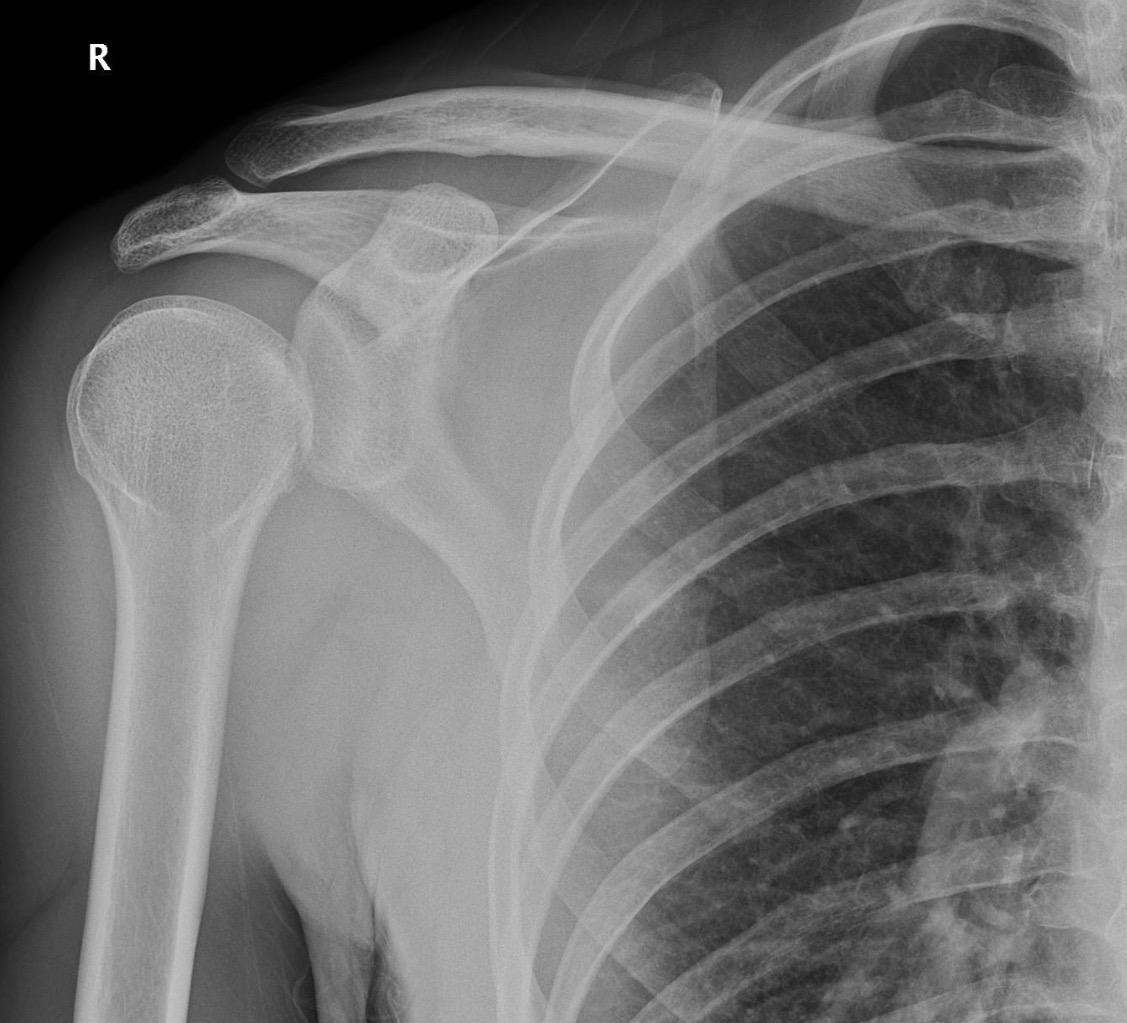

Shoulder dislocation (Posterior) ⭐

Less common

Lightbulb appearance

No overlap on lateral view